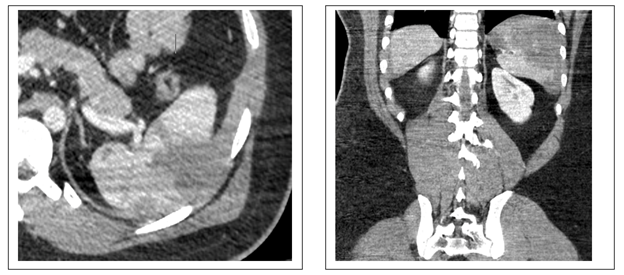

Bệnh nhân nam, 24 tuổi, quốc tịch Ả Rập Xê – Út, vào viện vì tai nan giao thông. Bệnh tỉnh, da niêm hồng nhạt, than đau vùng hạ sườn trái. Sinh hiệu thời điểm vào phòng cấp cứu cho thấy huyết áp 128/75 mmHg, nhịp mạch 75 lần/phút, nhịp thở 19 lần/ phút. Bởi vì huyết động ổn định, bệnh nhân được thực hiện cắt lớp vi tính bụng có thuốc tương phản. Trên hình ảnh CLVT ghi nhận vài đường rách nhu mô có độ sâu > 3cm, tụ máu gần hoàn toàn diện tích bề mặt, không thấy thuốc mạch thuốc cản quang và tổn thương mạch máu rốn lách. Đồng thời, hiện diện ít dịch quanh gan, dọc rãnh đại tràng hai bên. Các cơ quan khác không quan sát thấy tổn thương. Bệnh nhân được theo dõi bằng siêu âm bụng vào thời điểm sau 24h và 05 ngày sau chụp CLVT. Tổn thương nhu mô lách và tụ máu dưới bao ổn định, dịch ổ bụng giảm rõ rệt ở ngày thứ 05. Sau đó, bệnh được xuất viện sau 07 ngày điều trị.

Cắt lớp vi tính bụng có thuốc cản quang thì tĩnh mạch thời điểm nhập viện

Hình (a): rách nhu mô lách, tụ máu trong nhu mô

Hình (b): Tụ máu bề mặt lách